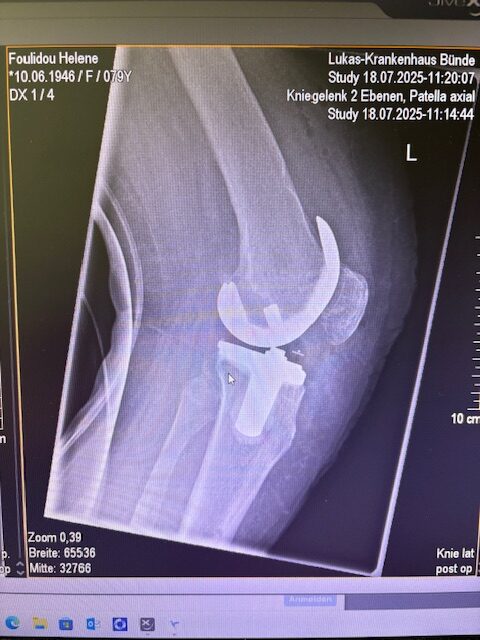

Τα εμφυτεύματα που χρησιμοποιήθηκαν στο γόνατο της ασθενούς είναι της Aesculap: E-Motion Pro, μηριαίο μέγεθος 4, κνημιαίο μέγεθος 4, με ενθέμα (inlay) 10mm.

Ήδη από τις πρώτες εβδομάδες, περπατούσε χωρίς πόνο, με βελτιωμένο εύρος κίνησης.   Η παθητική κίνηση κατα την έξοδο της ασθενούς από την κλινική ήταν E/F : 0-0-120 Επίσης πλήρη σταθερότητα του γόνατος σε κάμψη και έκταση.